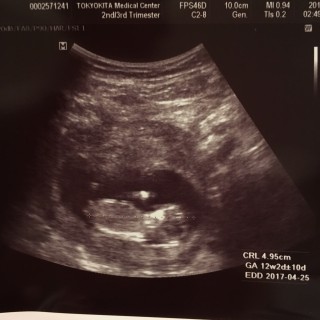

写真:12w2d:スパロウさん

2人目です。CRL4.77cmで少し小さめだそう。でも元気に動いてたので、問題はないとの事。上は男の子。次はどっちかなー